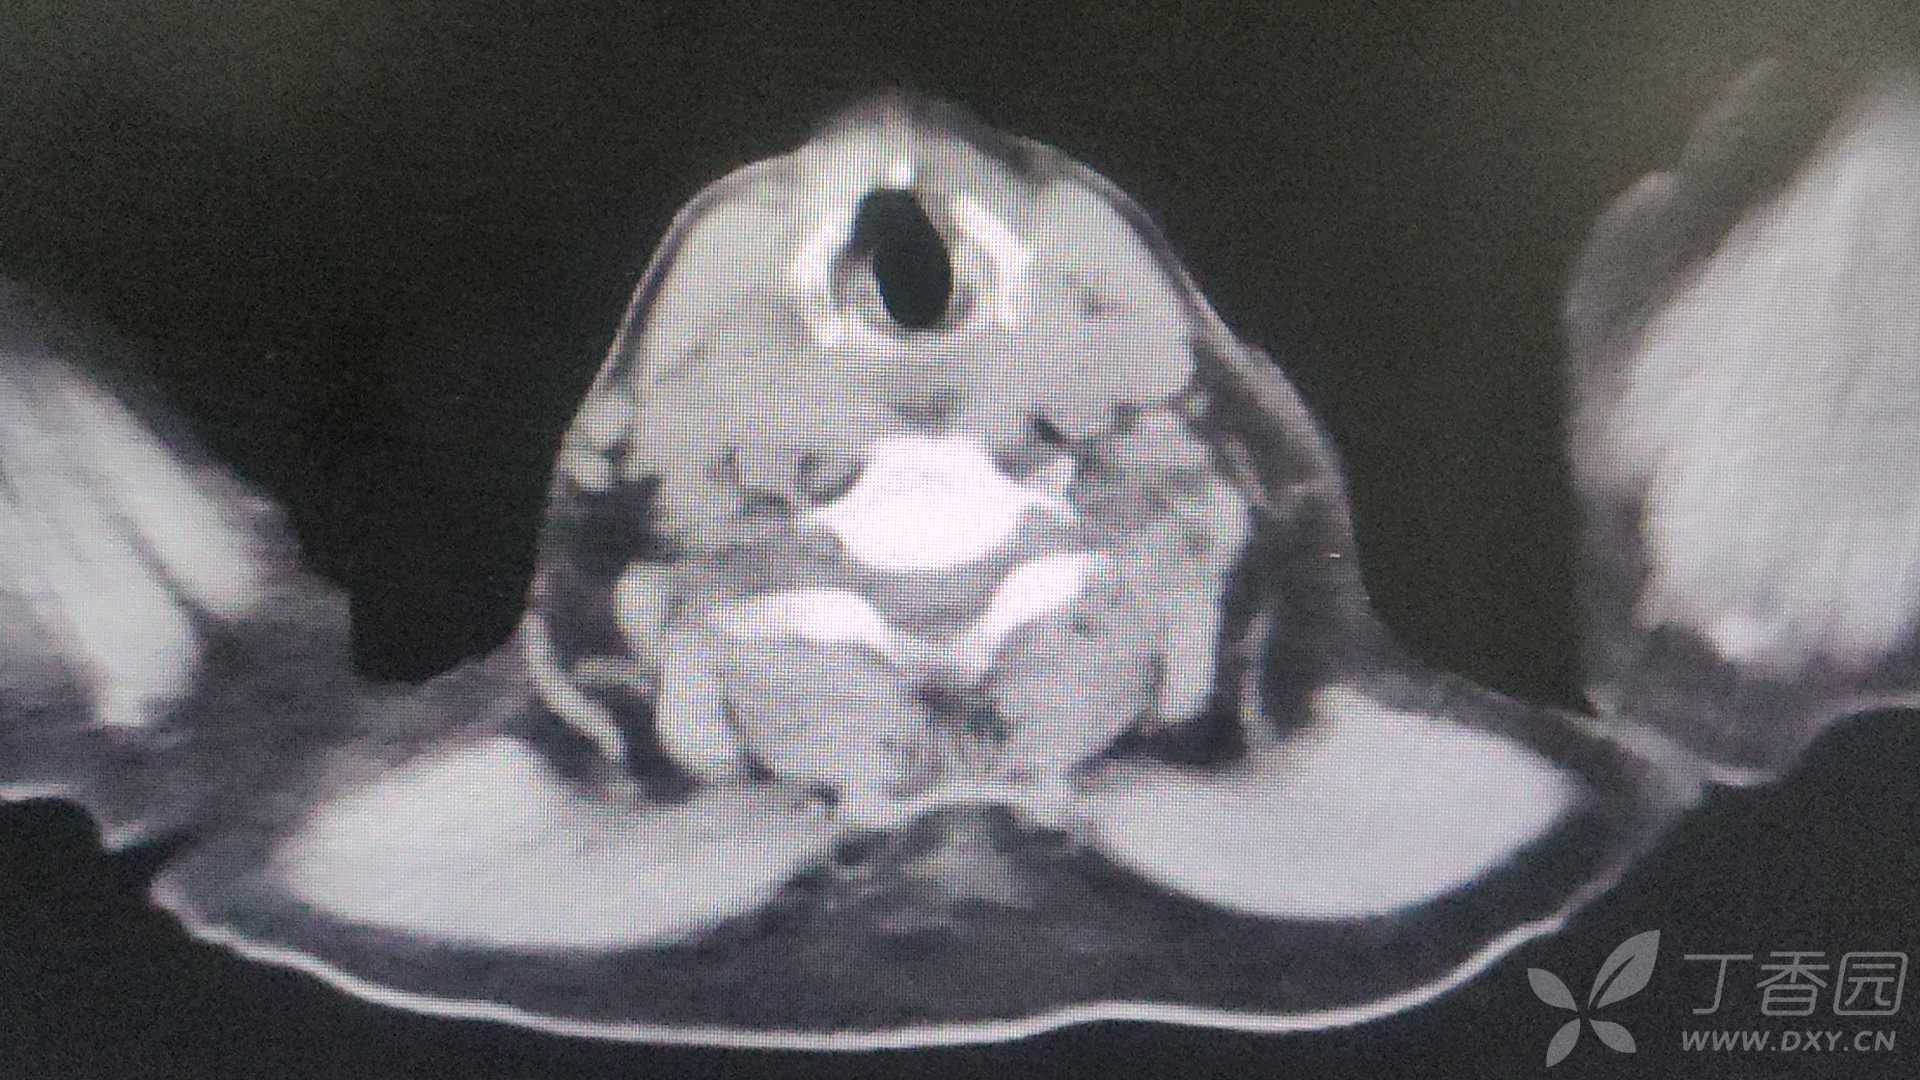

问题:原发病?心衰?可是指标不高,肺栓塞?可是ddi正常。慢阻肺?既往无呼吸道疾病史。呼衰?血气似乎还好,也没有缺氧。到底是什么原因呢。食管下壁增厚有没有关系?